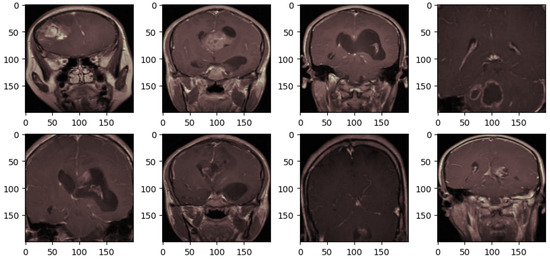

After all those techniques, the brain tumor MRI scans are obtained as depicted in Figure 4. These preprocessing steps systematically refine the images, ensuring that relevant features can be effectively focused on by the deep learning model. Unnecessary areas are removed through cropping; clarity is enhanced by noise removal; visual representation is standardized by applying a consistent colormap, and uniform input dimensions are ensured by resizing. This process aims to optimize the dataset for improved model accuracy in medical imaging tasks.

Figure 4.

The brain tumor MRI after preprocessing.

As depicted in Figure 5, a comparison of four sets of brain tumor MRI scans before and after image augmentation is illustrated. The first row displays a random selection of four images from the training set that have undergone preprocessing, as shown in Figure 4. The second row presents the same images after applying image augmentation.

Figure 5.

The brain tumor MRI before and after augmentation. (a–d) correspond to the original images, while (a′–d′) correspond to their augmented versions.